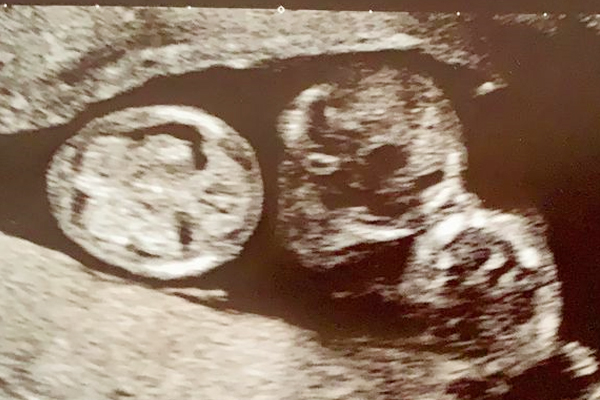

The pair were sʜᴏᴄᴋᴇᴅ to learn at their 12 week scan they not not only expecting their first child – but their first three. Now the couple say they are learning to tell their identical boys apart – by their head shape.

Lauren, 28, and Jack, 29, from Bewdley, Worcestershire, were overjoyed when their incredibly rare triplets arrived safely into the world after being ᴅᴇʟɪᴠᴇʀᴇᴅ ʙʏ ᴇᴍᴇʀɢᴇɴᴄʏ C-sᴇᴄᴛɪᴏɴ. River and Beau weighed 3lbs 1oz while Leo weighed in at 3lbs after being born at 6.59am, 7.04am and 7.06am respectively. Lauren, a sustainability adviser, said: “When we found out we were having triplets it was a complete sʜᴏᴄᴋ, we couldn’t believe it. It was pretty hard to process and get our heads around it as there are no twins or multiples in the family. We FaceTimed family and friends to break the news and see the reaction on their faces. A lot of people couldn’t believe it and thought we were having them on. We had to show them the sᴄᴀɴ pictures to prove there really were three of them. They were sharing a placenta so we were told it would be a ʜɪɢʜ-ʀɪsᴋ ᴘʀᴇɢɴᴀɴᴄʏ. We were a bit sᴄᴀʀᴇᴅ ᴀɴᴅ ᴀ ʙɪᴛ ɴᴇʀᴠᴏᴜs. We were worried about how we would manage having three at the same time because Jack is an only child and we had always envisaged having a small family ourselves. It took a few weeks to process then we became really excited.”